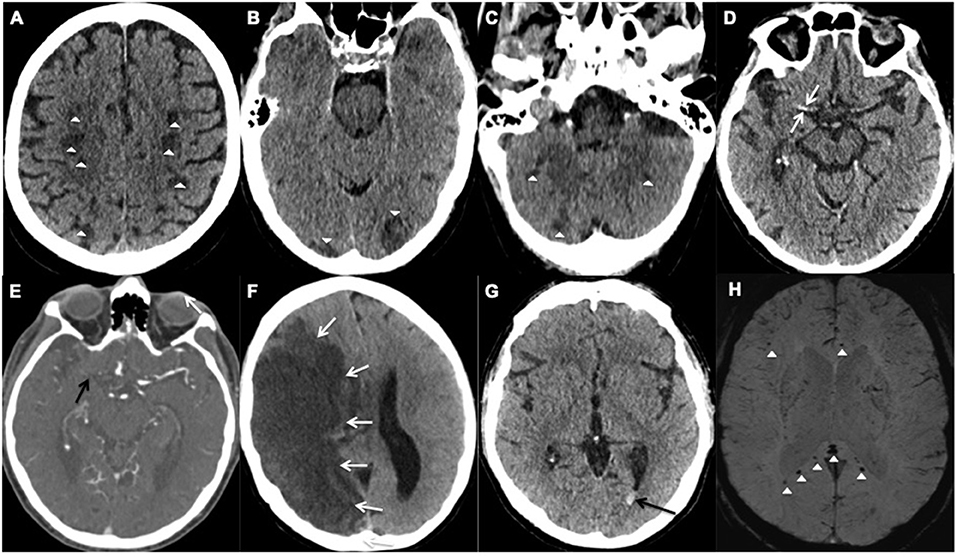

This #NeuroImage article highlights a case of acute postradiation lumbosacral plexopathy: https://t.co/K7yWRY7owf #NeuroTwitter